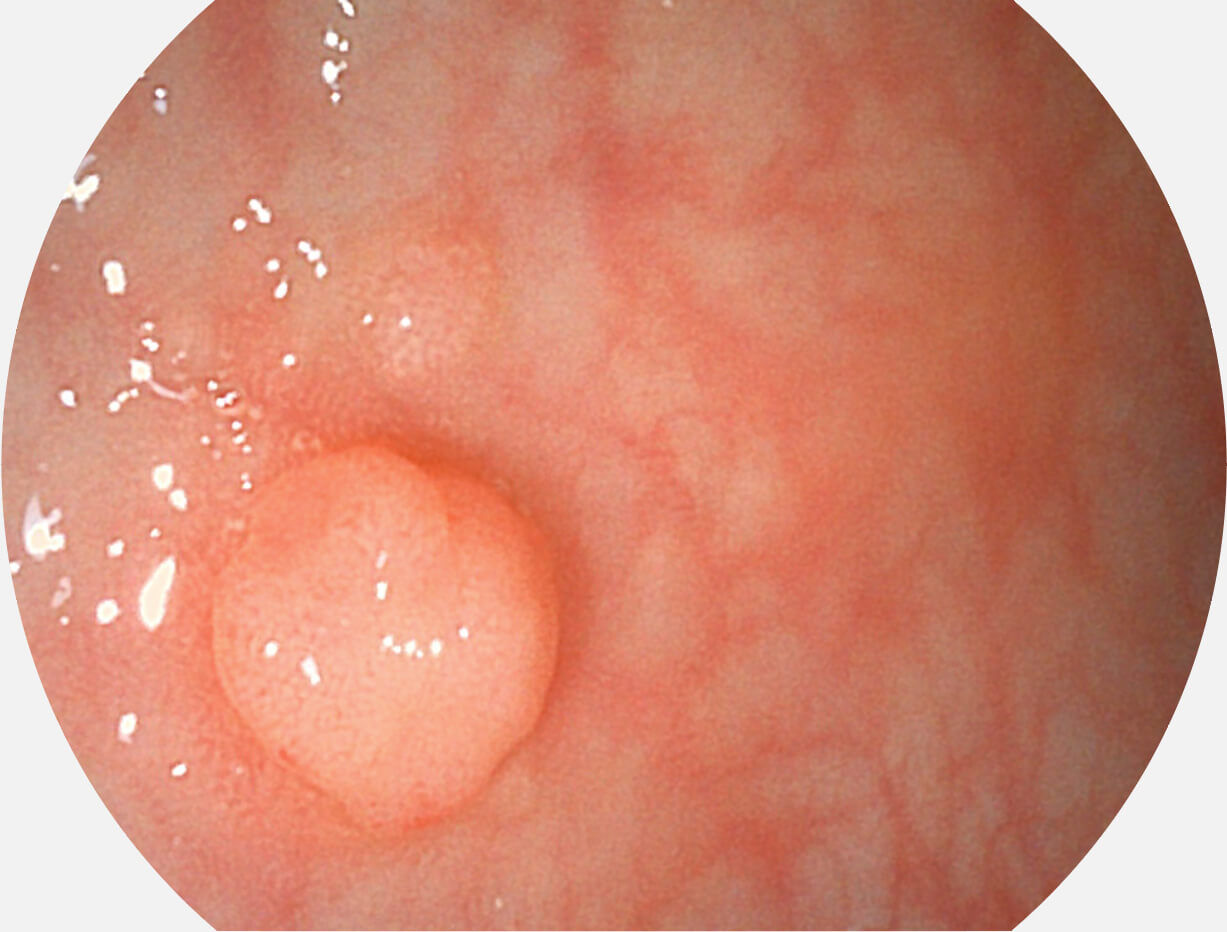

Spectral Focused lmaging, SFI

图像具有高亮度、高黏膜血管颜色对比度的特点,且不改变粘液、食物残渣、粪便的基本颜色,可在中远景下进行观察,助力消化道早期疾病的诊断。

白光图像

SFI图像